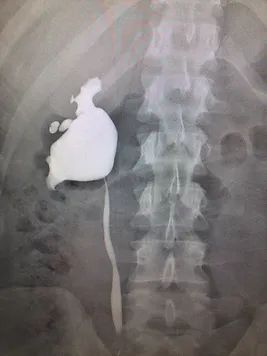

A hormone-secreting tumour that can occur in the adrenal glands. Phaeochromocytomas usually develop in the small glands on top of the kidneys (adrenal glands). They most commonly affect people between the ages of 20 and 50, but can occur at any age. Because of hormones secreted, symptoms include high blood pressure, sweating, rapid heartbeat and headache. Surgery to remove the tumour is usually required.